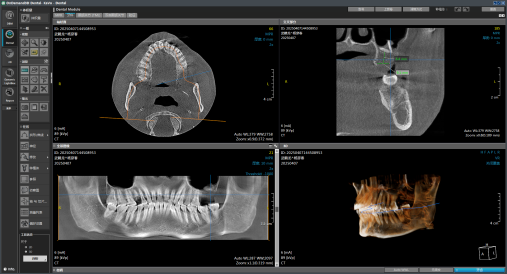

面对武先生到院拍的 CT 影像,杨彦春主任团队启动「复杂病例三阶评估机制」:

1. 立体影像研判:通过锥形束 CT 三维重建,精准定位两块游离骨片位置